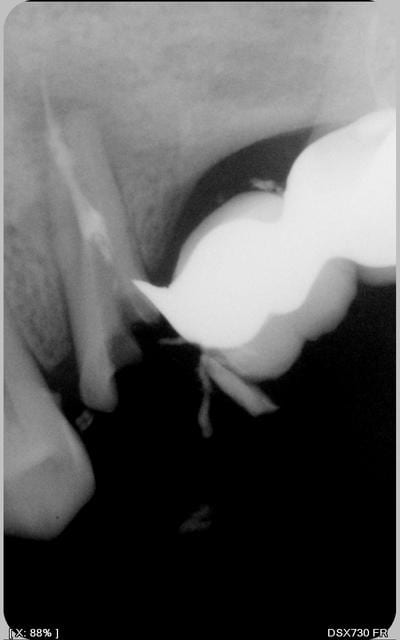

la radio.pas de poche paro

Images eb1m5g - Eugenol

heu... tu nous a remis la même radio...

Tu peux nous donner la radio post endo?

Tu as bien du avoir au moins deux canaux, non?

Ouh là, je sens qu'il va y en avoir qui ne vont pas être d'accord ;)

Ca n'a pas saigné ?

oh la jolie perf. et tu comptes vraiment garder cette dent ?

gloups! apparemment tu n'as pu trouver qu'un seul canal.

Pas de possibilité de trouver le deuxième? Pas de lumière canalaire visible à la radio en tout cas.

Bon, sincèrement, suis pessimiste, ton cône dépasse pas mal de l'apex apparemment ou est-ce un artefact de la radio?

ce n'est pas un artefact et a mon sens, il n'y a pas de perf

apex ouvert

un seul canal arrivé à etre traité

dépassement apparent de cöne

je ne conserverai pas surtout en repilier de bridge

et donc implants à envisager

Azerty, je suis très pessimiste!

Le tenon originel était déjà dévié en direction de la furcation.

Il semble que lors de la reprise tu as poursuivi dans cette direction jusqu'à effraction dans le furcation.

Vu le rôle de pilier qui devrait échoir à cette dent, l'ensemble d'opérations qui consisterait à:

- reprendre le traitement au delà de la fausse route

- combler celle-ci au MTA

- cureter la furcation

- reconstituer le moignon par collage

me paraît un peu gonflé et le pronostic pour le moins réservé.

il n'y a qu'une seule solution_-l 'extraction.

Pour le pessimisme,je suis d'accord avec toi Mark,mais pour l'axe du tenon ,j'ai l'impression

qu'il etait dans l'axe du canal,il me semble par contre que le trajet pris par Azerty,est différent